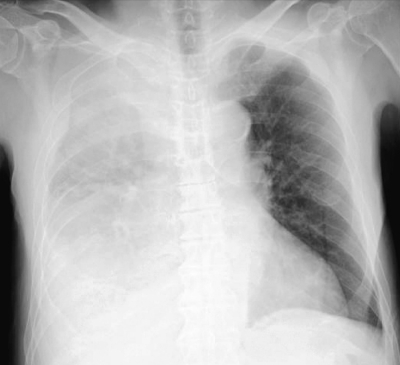

検査所見:血液所見:赤血球 355 万、Hb 12.1 g/dL、Ht 36 %、白血球 16,500 (桿状核好中球 25 %、分葉核好中球 65 %、好酸球 1%、単球 2%、リンパ球 7%)、血小板 40 万。血液生化学所見:総蛋白 5.9 g/dL、アルブミン 2.2 g/dL、AST 29 U/L、ALT 18 U/L、LD 173 U/L(基準 176〜353)、ALP 223 U/L(基準 115〜359)、γ-GTP 44 U/L(基準 8〜50)、CK 260 U/L(基準 30〜140)、尿素窒素 35 mg/dL、クレアチニン 1.6 mg/dL、血糖 161 mg/dL、HbA1c 5.7 % (基準 4.6〜6.2)、Na 131 mEq/L、K 4.3 mEq/L、Cl 97 mEq/L、Ca 8.4 mg/dL。CRP 31 mg/dL。動脈血ガス分析(room air):pH 7.55、PaCO2 32 Torr、PaO2 56 Torr、HCO3- 28 mEq/L。心電図で異常を認めない。臥位のポータブル胸部エックス線写真と胸部CTとを別に示す。

この画像所見をきたす原因として最も考えられるのはどれか。